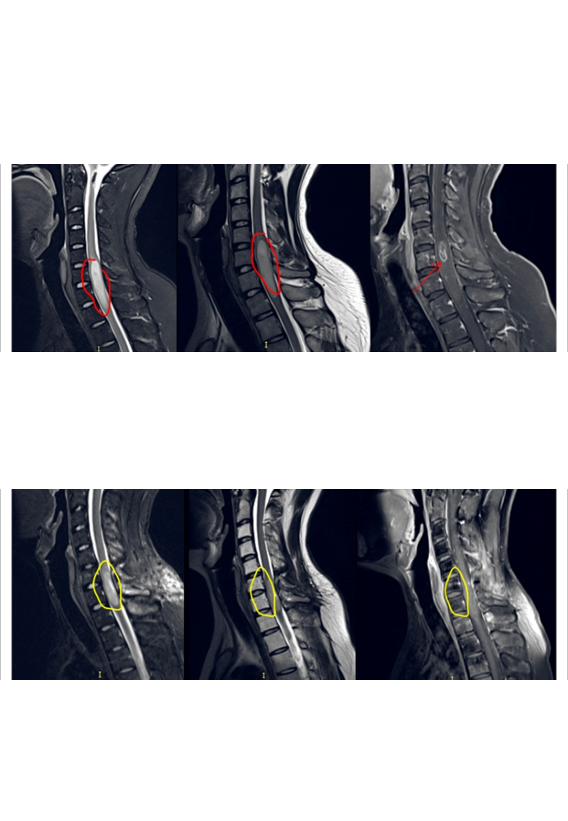

“肿瘤位置太不同、手术困难太大,残疾的可能性很大……”一位22岁髓内肿瘤占位的男士,颈后部疼痛,手臂麻木半年。咨询了国内一些大医院,医生们都这样告诉他。好在咨询了很多国外治疗办法,得知INC国际神经外科顾问团有位被国内尊称为“巴教授”对脊髓髓内、脑干等“手术禁区”内的肿瘤切除较为擅长。于是通过INC前往教授所在医院德国INI接受治疗,教授对其行髓内占位切除术、颈5-6椎体成行术,瘤体强化部分被完整切除。术后10天出院,精神状态佳。

胶质瘤是起源于神经胶质细胞的肿瘤,可以发生于大脑及脊髓的任何部位,而侵犯颅内脑干同时延伸累及颈髓甚至胸髓,这样病变范围广的胶...

脊髓2级胶质瘤可治愈吗?脊髓2级胶质瘤相对于更高级别的恶性胶质瘤来说,预后相对较好,但通常不能被定义为完全...